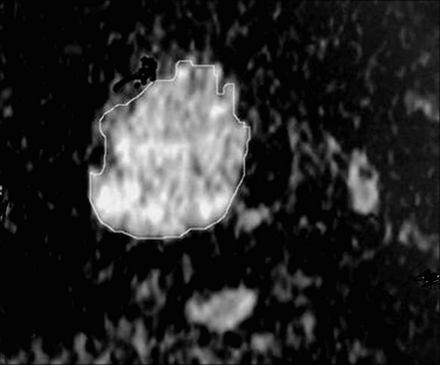

The 3 radiologists sharing in the study determined by consensus whether the ADC maps were acceptable for further analysis. Special attention was paid to image distortion by susceptibility artifacts. A quantitative analysis of the diffusion-weighted MR images was made. All images were interpreted by 1 radiologist specializing in head and neck imaging. The region of interest was drawn by 1 radiologist by electronic cursor around the thyroid nodules in the ADC map, and the ADC value was measured, as shown in Fig 1. In case of thyroid nodules with mixed solid and cystic components, the region of interest surrounded the solid portion to avoid the cystic part if possible because it could give a falsely elevated ADC value. The region of interest was placed around the cystic area in patients with thyroid cysts. Discrimination between the cystic and solid nodules was guided by sonographic examination.

Measurement of the ADC value of a thyroid nodule in an ADC map image. The region of interest is drawn around the thyroid nodule, and the ADC value is measured.